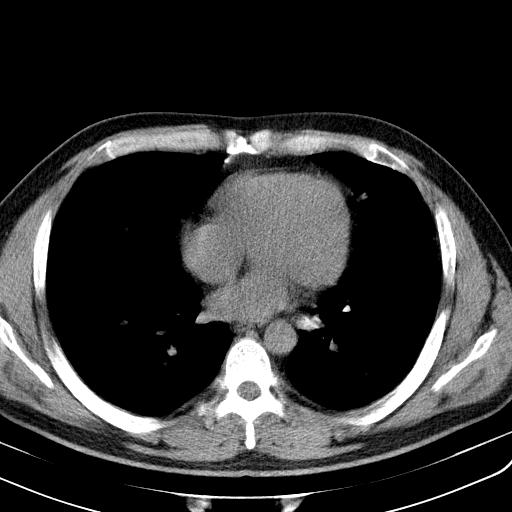

两肺散在大小不等小结节影,下野较多,纵隔淋巴结增大。考虑:1、慢性血播性肺结核;2、霉菌病?3转移瘤待排。

该病人肺内多发结节,右肺门似有肿大淋巴结,肺结节病也要考虑

双肺多发散在结节影,部分边界不清,延支气管分布;纵隔内多发小结节(淋巴结)影...

考虑

1.双肺转移ca及纵隔淋巴结转移;

2.特殊类型感染(霉菌)?

3.韦氏肉芽肿?

双肺散在多发类圆形结节灶,边缘较光滑,纵隔淋巴结肿大,考虑转移瘤

双肺及胸膜下见多发结节影,最大直径约0.4,内密度均匀,中纵隔腔静脉后见小淋巴结影。